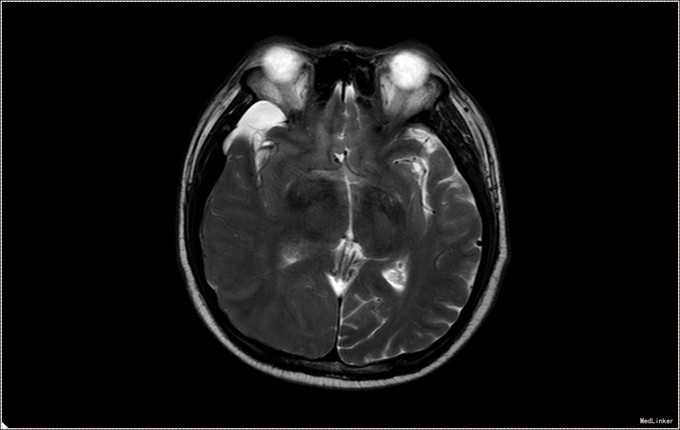

患者,男,53岁。以“左侧肢体疼痛伴无力1周”为主诉入院。患者1周前无明显诱因出现左侧肢体无力,伴酸痛,头部闷胀感,症状持续不缓解,于我院就诊,行头部CT及MR提示右侧顶枕叶硬膜下血肿。右侧额颞叶蛛网膜囊肿。患者为求进一步治疗,急诊以“硬膜下血肿”为诊断,收入病房。患者病来精神状态差,饮食睡眠可,二便可,体重无明显变化。否认近期头部外伤史。

入院查体:T:36.5℃ ,P:68次/分 ,BP:130/80mmHg , R:16次/分。步入病房,自主体位。神清语明,问答准确,查体合作,精神状态良好,定向力完整。粗测视野正常,双侧瞳孔等大正圆,D≈3.0mm,双侧眼球活动自如,对光反射灵敏。四肢活动自如,左侧肢体肌力V-级,右侧肢体肌力Ⅴ级,肌张力正常。深浅感觉检查未见异常。头CT及MR提示右侧颞极蛛网膜囊肿,右侧亚急性硬膜下血肿

患者诊断明确,完善术前检查行局麻右侧钻孔冲洗引流术,予常规治疗。术后3天拔管,复查头CT硬膜下血肿消失,但脑组织膨胀不良。患者左侧肢体肌力恢复正常,无头晕头沉症状,顺利出院。